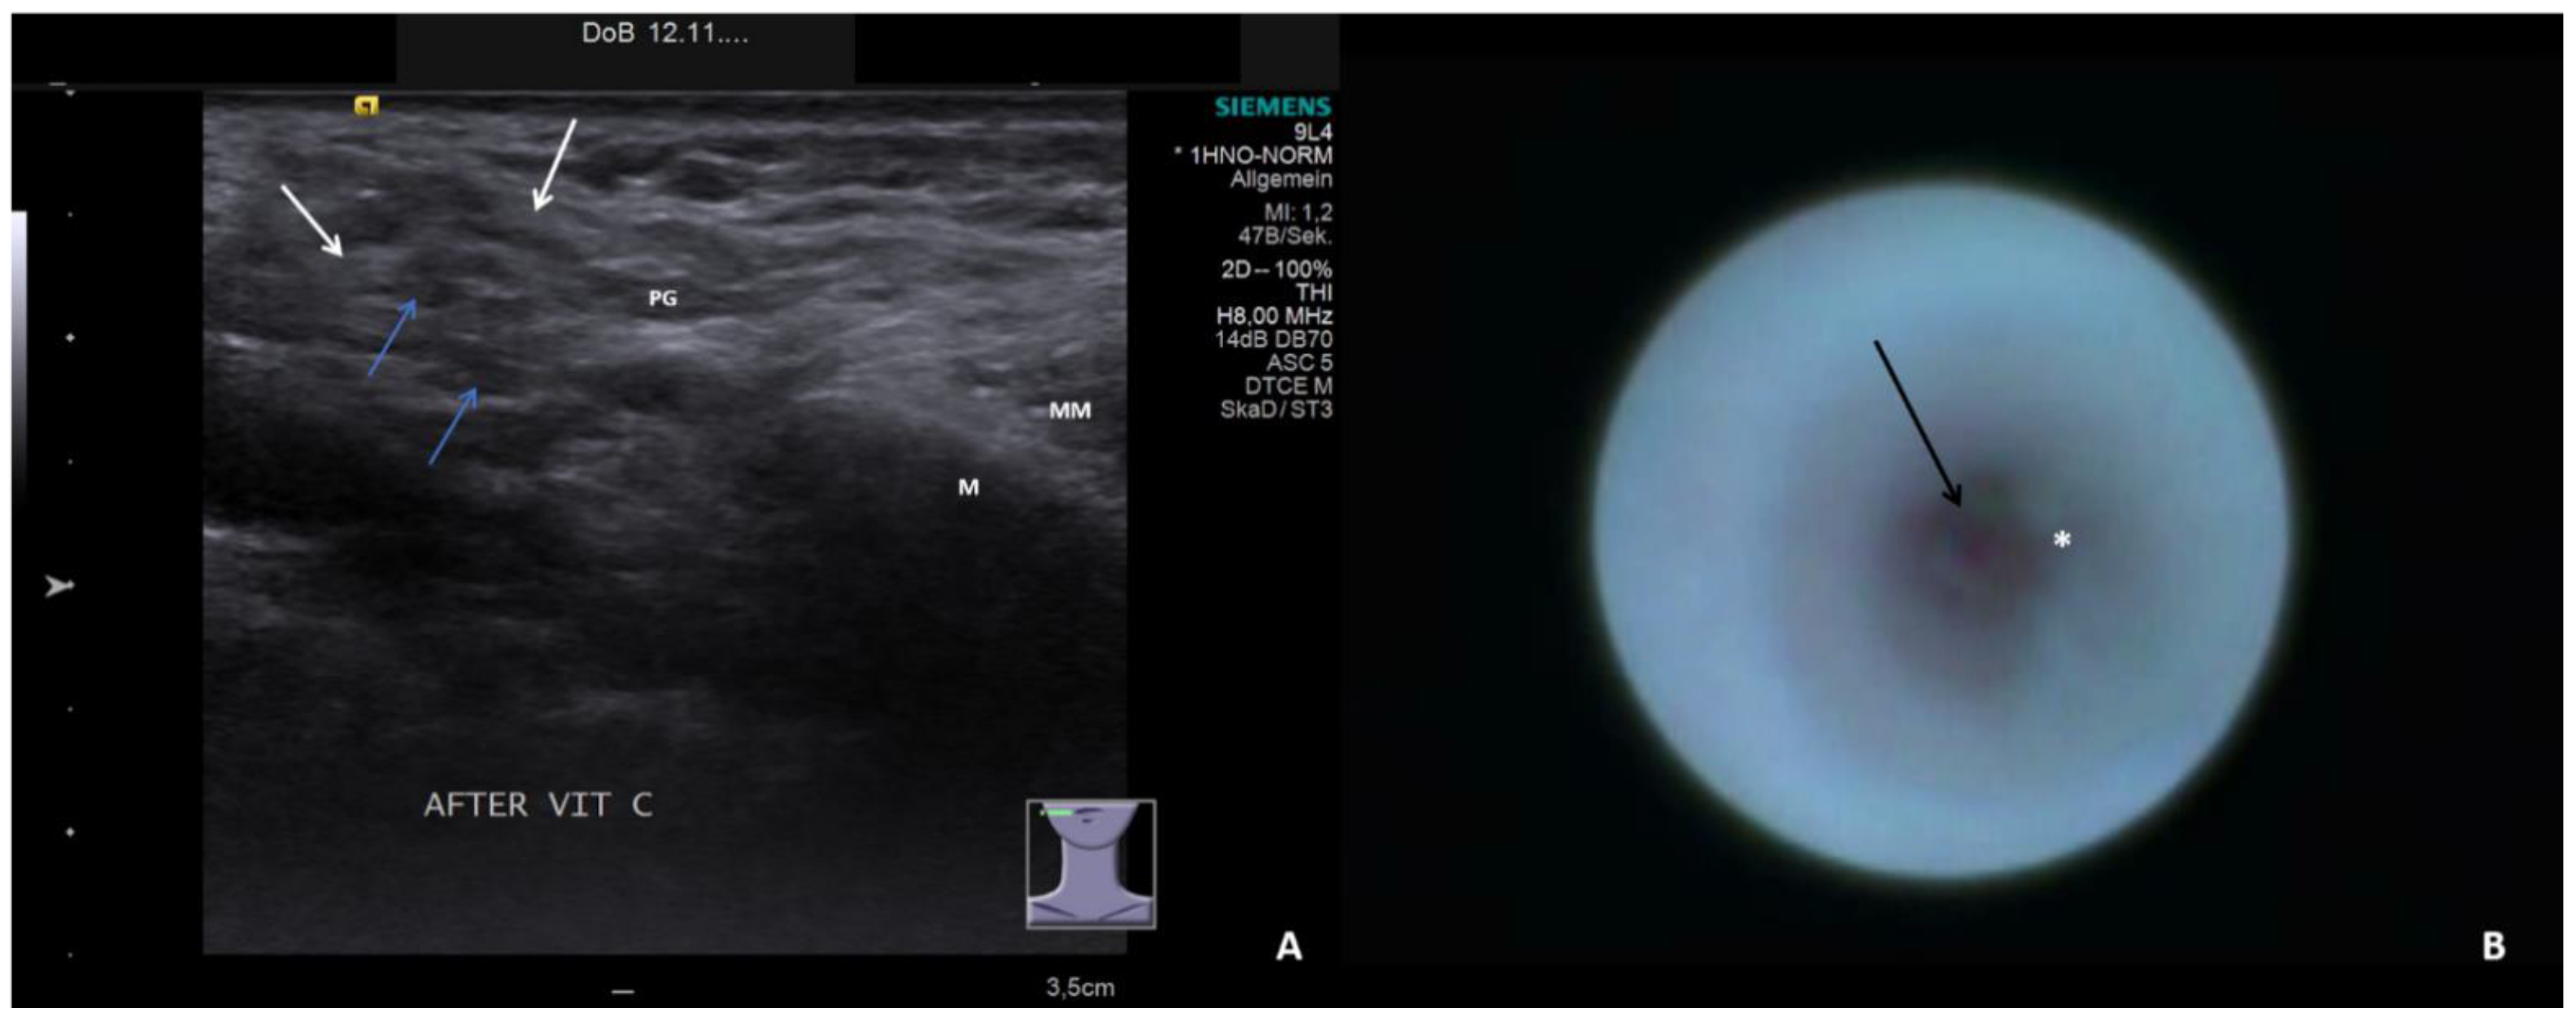

- Short duct stenosis (≤1 cm; Figure 3B; Supplementary Video S3)